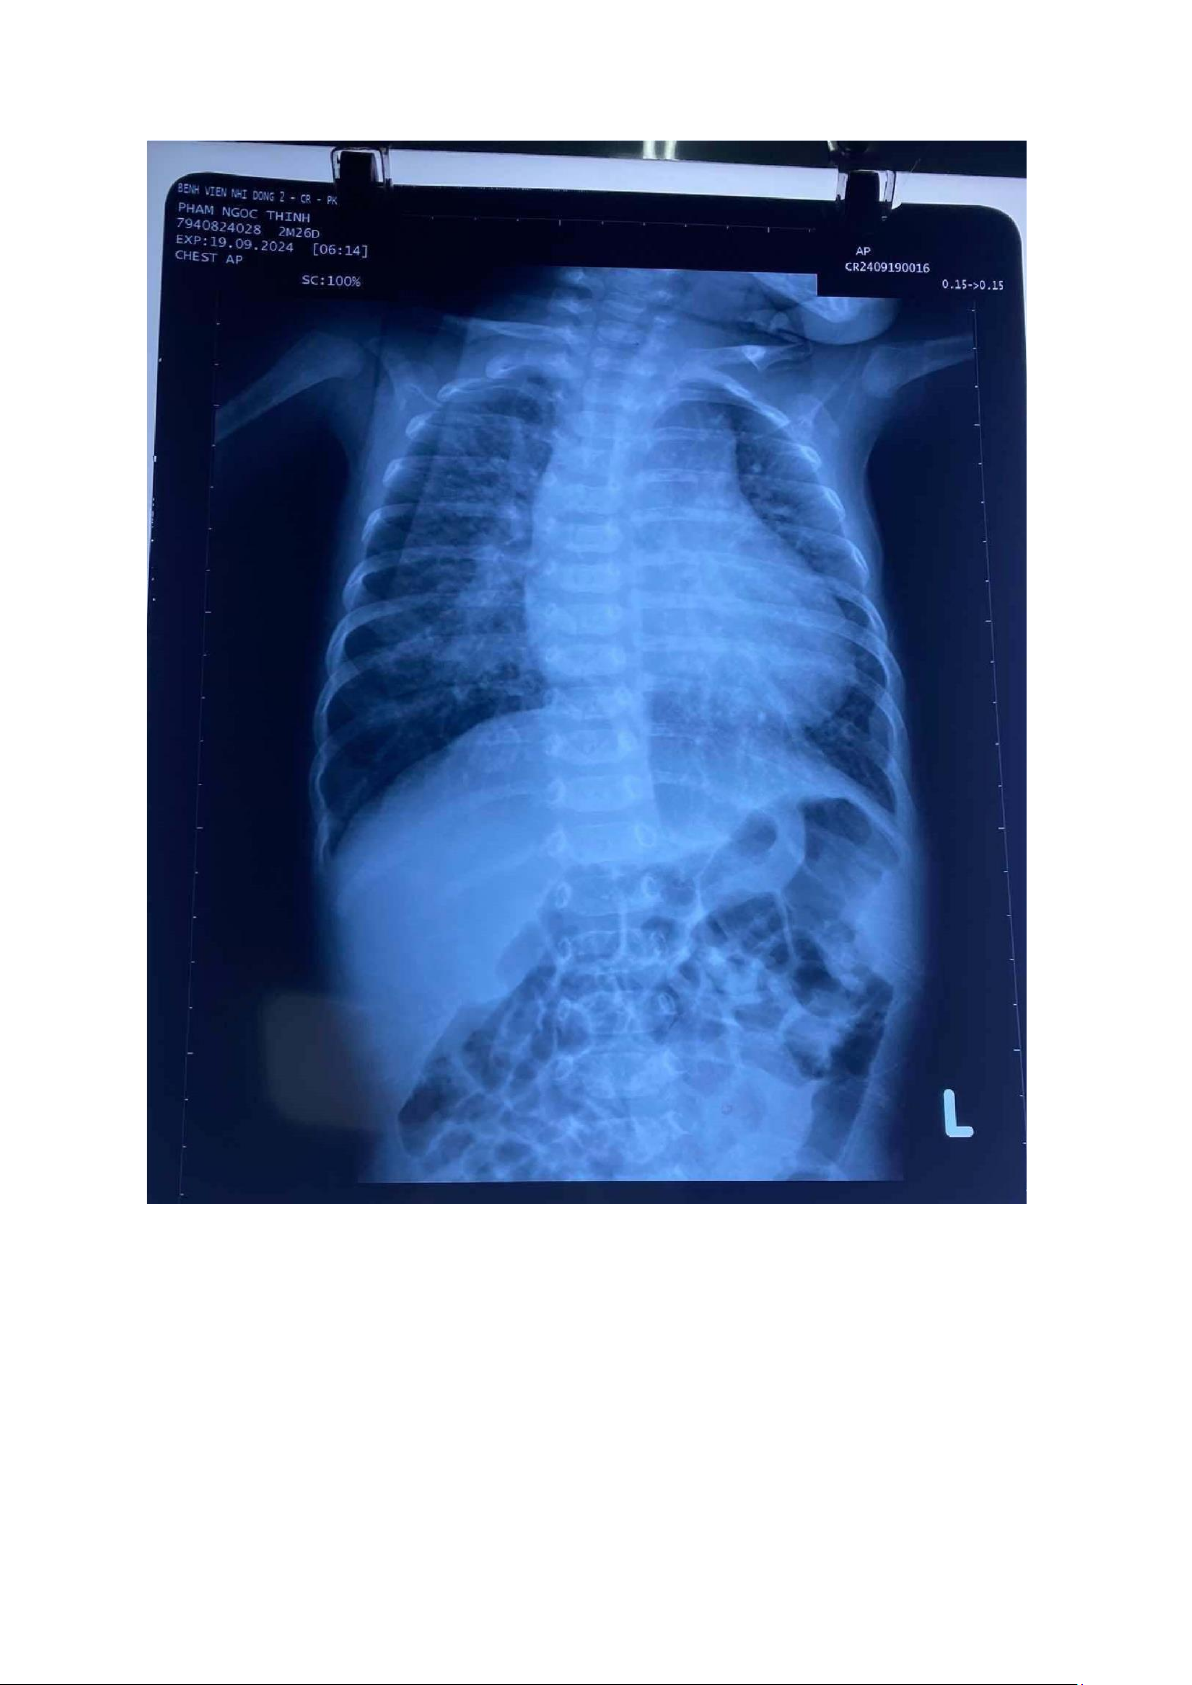

- Ferritin tăng 670 ug/L -> ề nghị thêm iện di Hb. 4. X-quang 19/9: 1. vị trí tim:

+ Situs solitus + Levocardia2. tuần hoàn phổi:+ rốn phổi ậm, tuần hoàn

phổi ra ⅓ ngoài 2 bên phế trường

→ tăng tuần hoàn phổi chủ ộng

2. kích thước tim và các cung tim 3. hình dạng bóng tim 4. 23/9: 5. Cấy àm: âm tính XII. Chẩn oán xác ịnh XIII. Điều trị 1. Maxapin 1g 210mg x 3 (TMC)